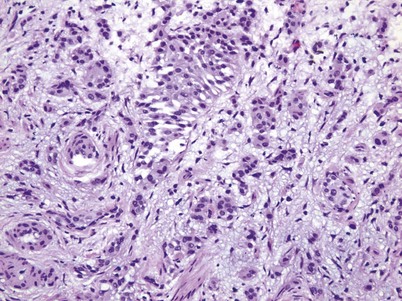

Muscle-invasive urothelial carcinoma is by definition high grade and is composed of cancerous cells extending through the lamina propria into the deep muscle bundles. There are rare cases of metastases to the deep muscle, but the overwhelming majority of cases are a direct extension from a surface urothelial carcinoma through the lamina propria into the deep muscle.

The American Joint Commission on Cancer in combination with the International Union Cancer Consortium meets on a regular basis to determine the tumor, nodes, and metastases (TNM) staging classifications. The 2009 staging system is shown in Table 80–7 (Edge et al, 2010). Ta and CIS disease have no invasion of the basement membrane, but endophytic growth of low-grade tumors into the lamina propria is possible, and cancer can occur in Von Brunn nests (Sung et al, 2006, Jones et al, 2007). T1 disease, as mentioned earlier, can be divided into T1a and T1b disease (Smits et al, 1998). The subdivision is based on the muscularis mucosa, which comprises thin wavy vesicles of muscle within the lamina propria that are associated with large vessels and lymphatics (Fig. 80–12). Some investigators substitute the presence of this large-vessel lymphatic layer for the muscularis mucosa when dividing T1a and T1b disease (Lopez-Beltran and Cheng, 2003). Unfortunately, muscularis mucosa is only identified in 15% to 80% of bladder biopsy specimens and in 90% of radical cystectomy specimens (Cheng et al, 1999; Sozen et al, 2002; Lopez-Beltran and Cheng, 2003; Lopez-Beltran, 2008). The prognostic significance of T1a and T1b disease is inconsistent because of the lack of muscularis mucosa in many bladder biopsy specimens. Essentially, the T1a and T1b stratifications suggest that the deeper the tumor invades in the lamina propria, the worse the survival.